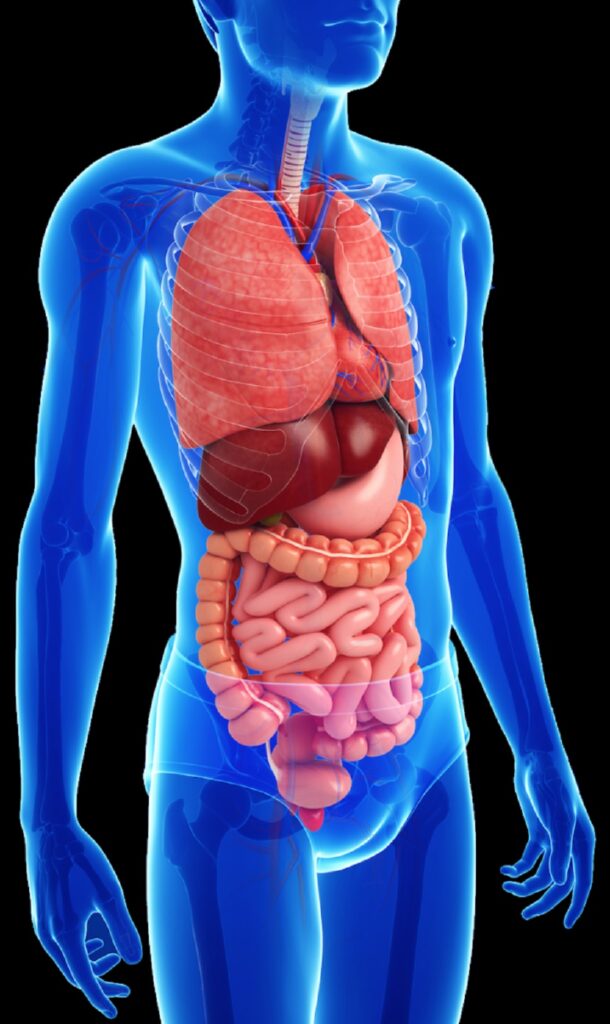

Sistema respiratorio

El sistema respiratorio es responsable del intercambio de gases entre el ambiente y el cuerpo, suministrando oxígeno a las células y eliminando dióxido de carbono.

Sistema digestivo

Elsistema digestivo descompone los alimentos en nutrientes que el cuerpo puede absorber y utiliza para obtener energía, crecimiento y reparación de tejidos.

Sistema Excretor

El sistema Excretor elimina desechos líquidos y regula el equilibrio de agua y electrolitos en el cuerpo.